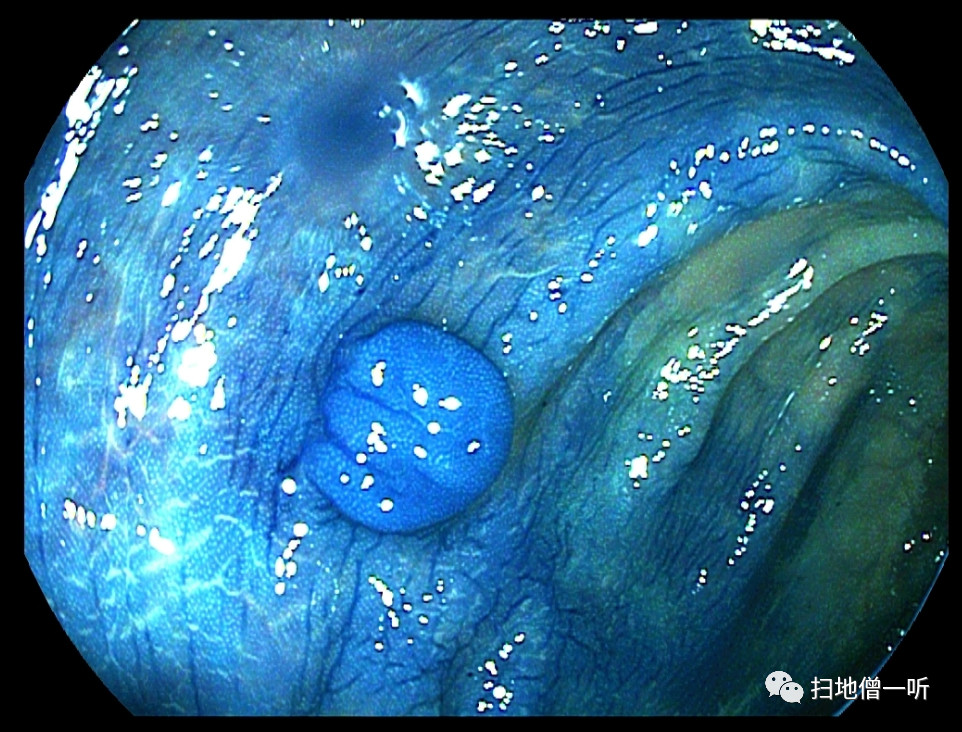

随后

乙状结肠又有个小隆起

就是这个货~

大图奉上请各位详细观察:

常规上染色看看

确实像亚蒂,但又似乎不是亚蒂

表面似乎太过光滑,并且

这息肉为啥长成了一张饼?

换成电镜染色再看看?

I-SCAN 1

I-SCAN 3

表面的边界不必说

蒂部为何感觉没有边界?

并且为啥感觉软塌塌?

心头的疑虑越来越多

这就不是息肉!

这是憩室内翻!

PS:从目前的技术的角度上来说,就算是憩室内翻也可以切掉,只要钛夹封闭完全是没有任何问题,但我想表达的是:诊断是一切治疗的前提!